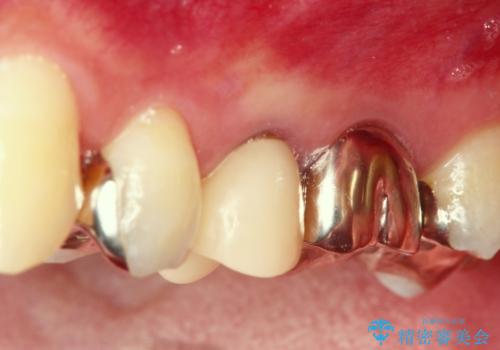

セラミックインレーと根管治療を伴うセラミッククラウン

X線写真より大きな根尖病変が認められ根管治療および補綴処置、手前の歯は虫歯の再発による銀歯のやりかえが必要な状態です。

セラミック治療の注意事項(リスク・副作用など)

- 天然歯を削ります

- 硬い素材は天然歯を傷つけてしまう場合があります

- かみ合わせや歯ぎしりが強すぎる方はセラミックが割れてしまう可能性があります

- 自費診療(保険適用外治療)となります